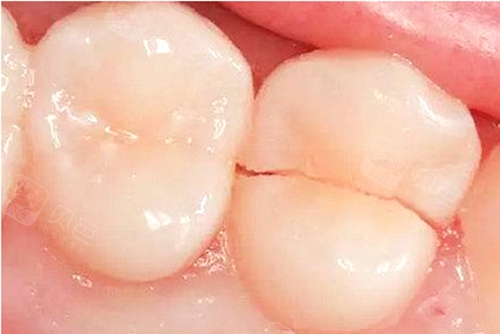

牙齿牙尖过尖、咬合过紧、牙齿发育不良等可导致牙齿出现裂纹,另外有的人习惯长期咀嚼硬物,甚至牙齿开啤酒盖等习惯,也可导致牙齿隐裂或缺损,严重的牙齿隐裂或缺损可致牙齿劈开且无法保留,导致缺牙。牙齿磨耗和楔状缺损也是导致老年人牙体和牙列缺损的主要原因。

隐裂的牙齿从中间劈裂开导致患牙无法保留